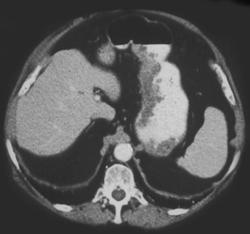

Pancreatic Cancer Causes Gastric Outlet Obstruction